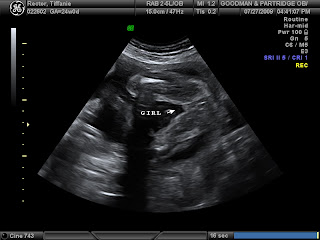

We had another ultrasound yesterday (7/27/09). We are at 24 weeks and just pushing right along. The ultrasound tech confirmed that Bethanie really is a girl because Bryan still wasn't believing it...but it's for sure! Her legs are extremely long and everything is still going great. Four chambers in the heart, beating beautifully...153 bpm. She weighs 1 pound 10 ounces right now. She's nice and healthy and happy...she was being shy yesterday. First she was trying to hide behind her arm...and then she was smooshing her face up against the placenta, guess she was too tired to be modeling. She had a long day yesterday jumping on her trampoline (my bladder). Haha. Anyway...everything's going well, so here are her 24 week ultrasound pictures. ENJOY!!